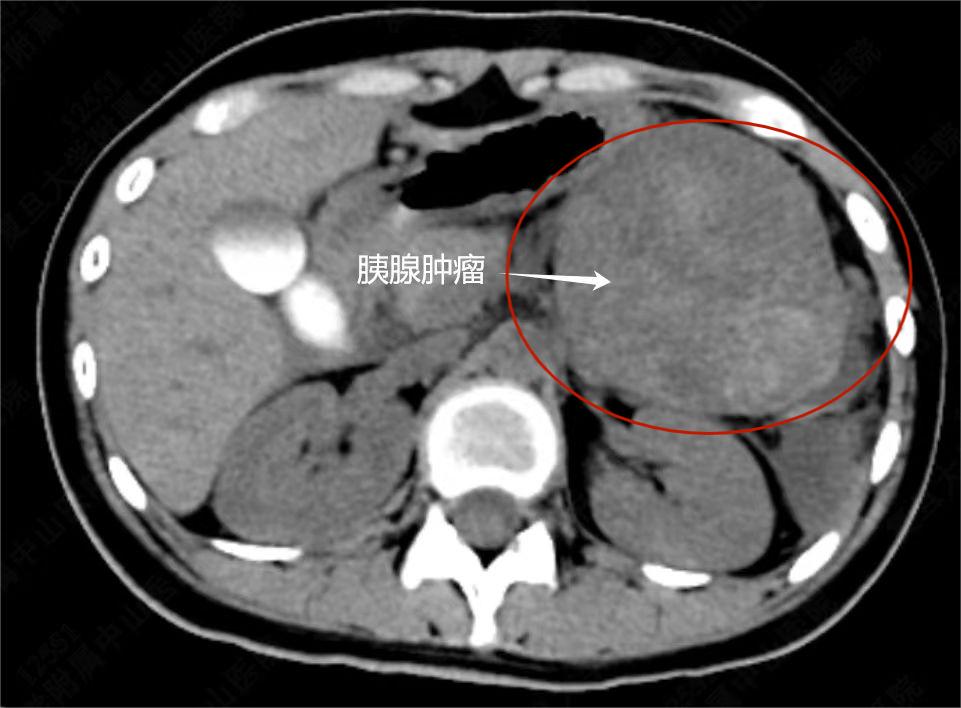

19岁患者娟娟(化名)术前影像片。本文图片均为复旦大学附属中山医院 图

5月20日,澎湃新闻(www.thepaper.cn)记者从复旦大学附属中山医院获悉,19岁的大一女生娟娟(化名)已于5月17日顺利出院。8天前,她因突发腹痛来到中山医院就诊,被发现胰体尾部长有一个直径约12厘米的巨大肿瘤,当时已有破裂迹象,一旦引发大出血,将危及生命。

中山医院胰腺外科副主任医师张磊接诊后,迅速将娟娟收治入院。专家团队讨论后,认为娟娟患有的是胰腺实性假乳头状肿瘤,肿瘤巨大且有破裂表现。通常这种情况,医生往往以开放式手术治疗为主,但这会在患者上腹部留下长约25厘米的疤痕。同时,因脾动静脉与胰体尾联系较为密切,通常切除胰体尾的时候,会一并切除脾脏。